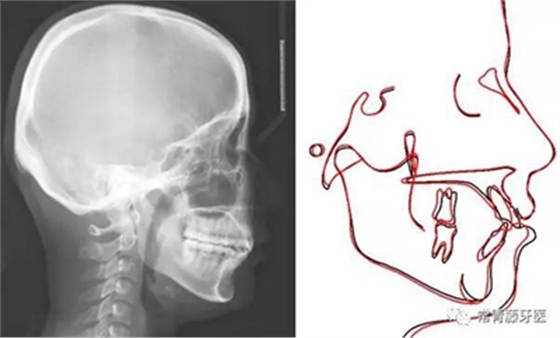

頭影測(cè)量顯示上下頜骨發(fā)育不足,且呈現(xiàn)骨性Ⅱ類(lèi)。

術(shù)前術(shù)后描記圖顯示上牙列整體遠(yuǎn)移有效,表現(xiàn)為磨牙遠(yuǎn)移及上前牙內(nèi)收(黑色術(shù)前,紅色術(shù)后)。